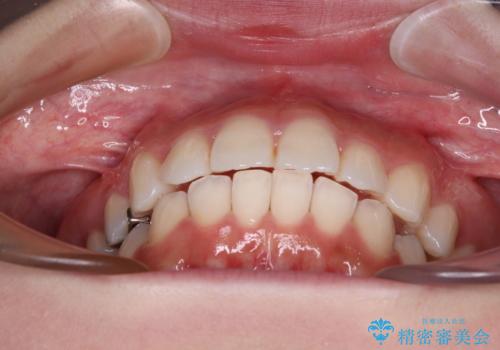

上顎歯列全体を後方移動させたことで唇に当たる感覚は改善され、更には上下の正中位置も合わせることができました。